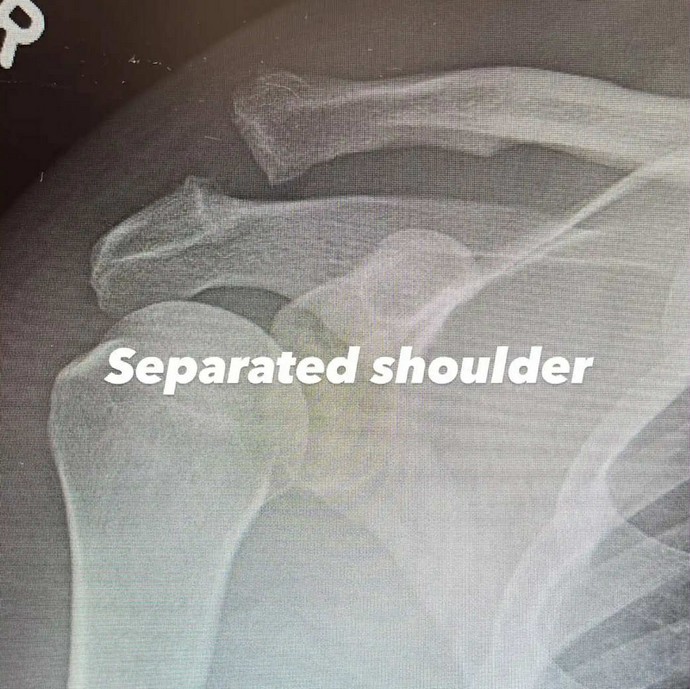

Στην πρώτη ανάρτηση σε Instagram Story, ο ηθοποιός μοιράστηκε μια ακτινογραφία του άνω βραχίονα και της περιοχής του ώμου.

«Διαχωρισμένος ώμος», έγραψε, ενώ ανάρτησε μια νέα φωτογραφία μετά την επέμβαση της ίδιας περιοχής. «Βιδωμένος ώμος. Υπέροχα», ήταν η λεζάντα της 2ης ακτινογραφίας, όπου φαίνεται μια μεγάλη βίδα που κρατάει τα οστά του στη θέση τους.